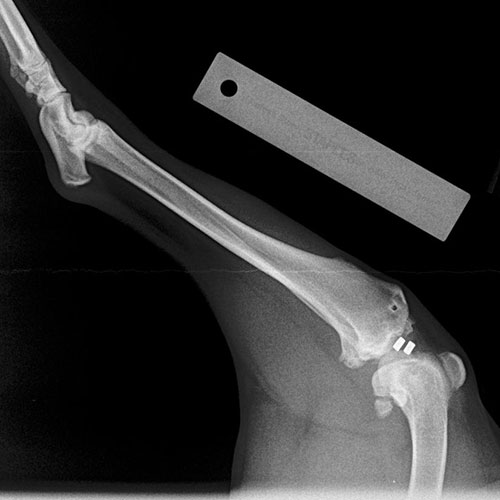

• Diagnosis: Our veterinarians use a combination of physical examinations, palpation tests like the cranial drawer test, and often radiographs to confirm CCL tears. Early diagnosis can prevent further damage to the joint.

• Surgical Repair: The most effective treatment for CCL tears, especially in active or large dogs, includes various techniques like extracapsular stabilization, TPLO (Tibial Plateau Leveling Osteotomy), or TTA (Tibial Tuberosity Advancement). These surgeries aim to stabilize the knee joint and reduce arthritis progression. Generally speaking, TPLO is superior to TTA, which is superior to extracapsular technique but our doctors will help you decide what is optimal for you and your pet.